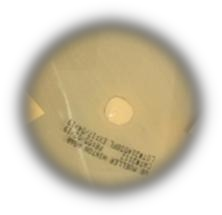

Table 5: The images of the inhibition zone of different antibiotic creams and musk 100% concentration on microbes

| N. M. | B. M. | M. W. | Antibiotic creams | |

| S. aurus | ![]() |

![]() |

Avocin Cream contains Clindamycin (Cleocin Phosphate) as an active ingredient. Clindamycin a semisynthetic bacteriostatic derivative of lincomycin,Lincosamide antibacterial that inhibits protein synthesis of the bacterial cell wall by binding to bacterial ribosomal receptor sites.(Shorr, R. I., Hoth, A. B., and Rawls, N.(2007) Lamifen Cream The active substance of the cream was weak compared to the results of musk and did not affect the vitality of the fungus. This indicates the severity of the resistance of the fungus to this active substance.